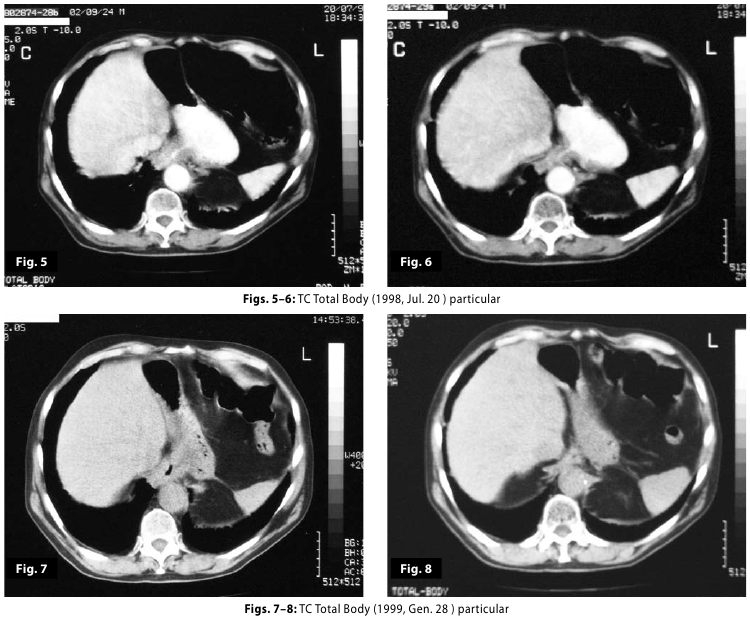

Figure5-6

Figure5-6-7-8